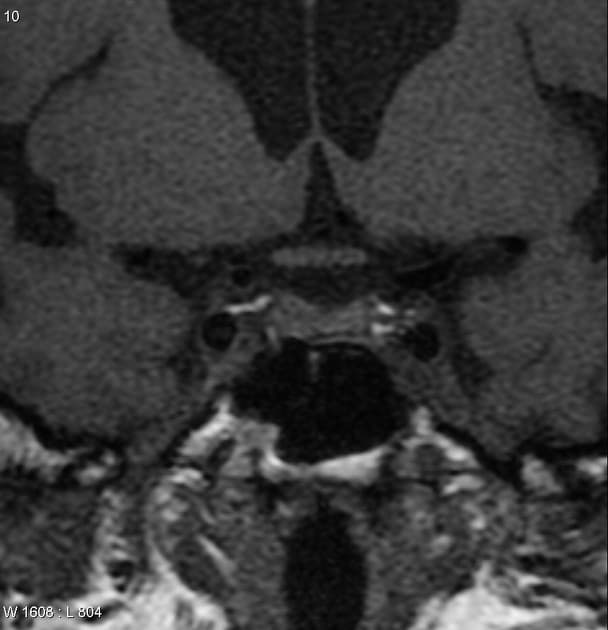

- Khối liên tục với cuống yên, làm giãn cuống này cả phía trên và phía dưới.

- Phù hợp với kiểu tăng quang đặc trưng và nằm trong cuống yên (infundibulum).

- Khối phù hợp với kiểu tăng quang đặc trưng và nằm trong cuống yên (infundibulum).

- Khối liên tục với cuống yên, làm giãn cuống cả phía trên và phía dưới.

- "Đặc điểm hình ảnh gồm khối u ranh giới rõ, tăng quang mạnh, liên tục với và làm giãn cuống yên."

U Pituicytoma là một loại khối u thần kinh đệm lành tính, phát triển chậm và hiếm gặp, xuất phát từ các tế bào pituicyte ở thùy sau tuyến yên hoặc cuống yên. Khối u thường biểu hiện như một tổn thương ranh giới rõ, tăng quang mạnh và liên tục với, đồng thời làm giãn cuống yên. Trên cộng hưởng từ (MRI), khối u thường có tín hiệu đẳng trên hình ảnh T1 và tăng quang đồng nhất sau khi tiêm thuốc cản quang. Việc không có dấu hiệu ác tính, không bệnh toàn thân và tổn thương ổn định dài hạn trên hình ảnh học làm tăng khả năng chẩn đoán u Pituicytoma, ngay cả khi chưa xác định bằng mô bệnh học. Các chẩn đoán phân biệt bao gồm u tuyến yên có liên quan đến cuống yên, u màng não và bệnh tổ chức bào Langerhans, những bệnh này có thể có hình ảnh tương tự. Tuy nhiên, vị trí đặc hiệu trong cuống yên và sự liên tục với cuống làm nghiêng về chẩn đoán u Pituicytoma. Điều trị thường mang tính theo dõi bảo tồn, đặc biệt ở bệnh nhân không có triệu chứng.